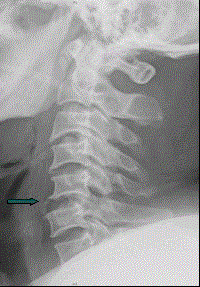

患者男,38岁,车祸伤后导致颈部疼痛、四肢瘫痪,排尿、粪失禁,ASIA分级C级,入院时间为伤后6 h,佩戴颈托入院。于急诊行颈椎正侧位X线片(如图)。...

问题 患者男,38岁,车祸伤后导致颈部疼痛、四肢瘫痪,排尿、粪失禁,ASIA分级C级,入院时间为伤后6 h,佩戴颈托入院。于急诊行颈椎正侧位X线片(如图)。 根据患者颈椎X线片的显示,考虑此患者最可能的受伤机制为

选项 A、垂直压缩型 B、混合型 C、过伸型损伤 D、屈曲牵张型 E、屈曲压缩型

答案 C